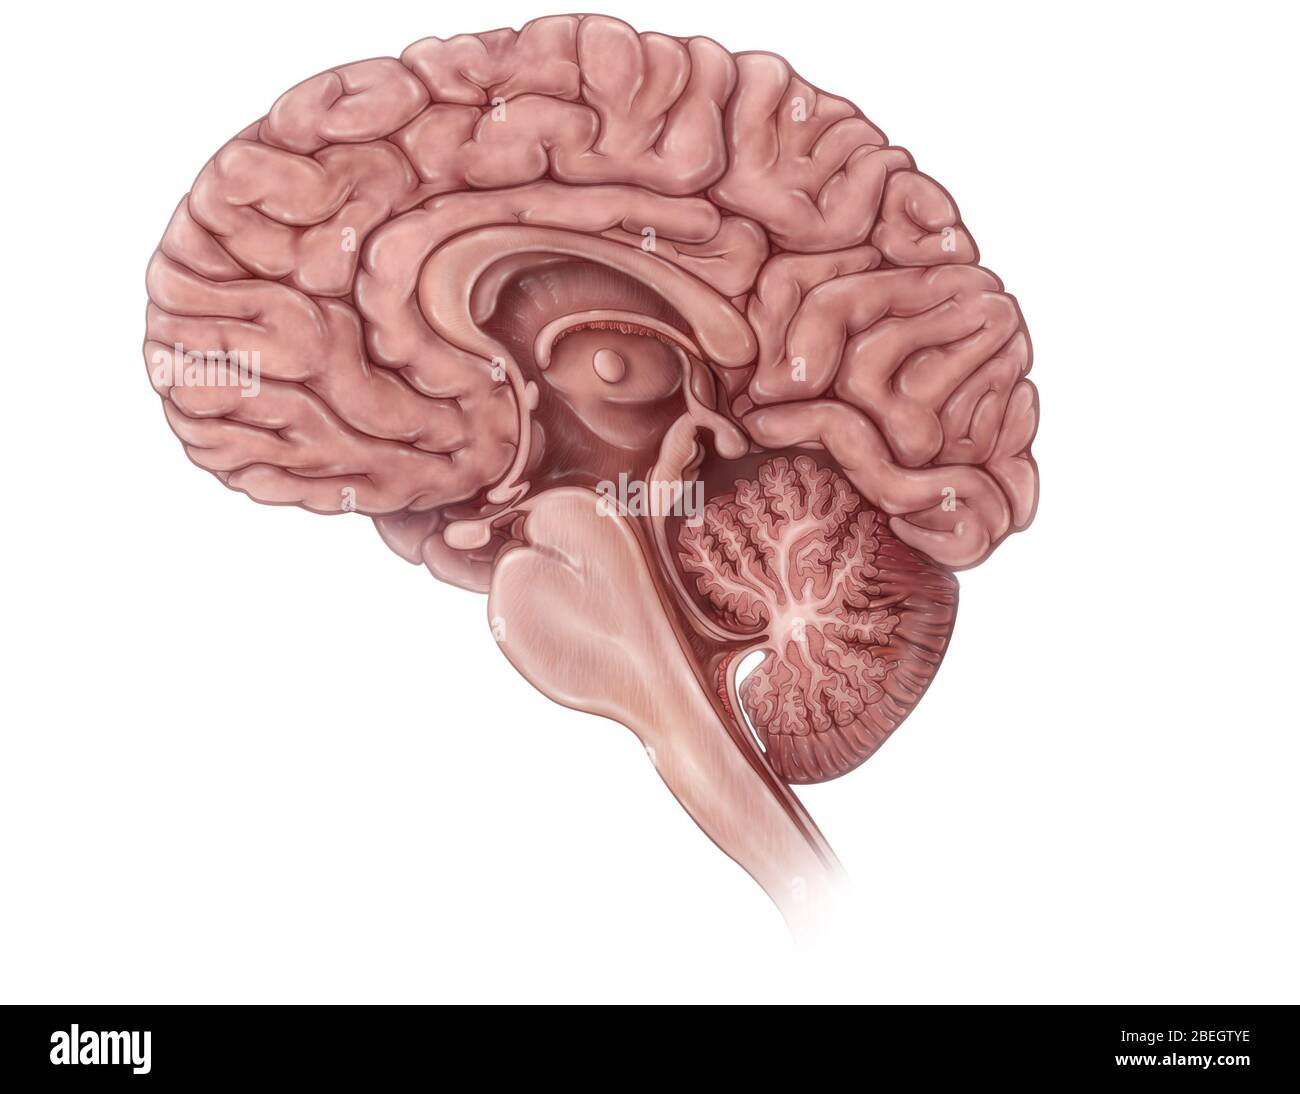

RMBCE641–Sagittale Abschnitt des menschlichen Gehirns, Darstellung von Strukturen der zerebralen Ventrikel, Kleinhirn und Hirnstamm.